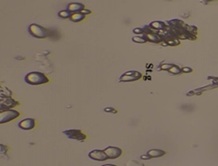

Shigru (Moringa oleifera Lam..) is one of the most important plants having nutritional as well as medicinal value in Ayurveda. This present study has been carried out to establish the stem bark of plant for its morphological, microscopical and physicochemical characters with different phytochemical qualitative tests as per API and Sophisticated analysis such as High-Performance Thin Layer Chromatography (HPTLC). Microscopy of stem bark showed Phloem, Rosette crystal, Resin duct, Stone cell, Medullary rays, Gum secretion, Crystal, Stratified cork. Powder microscopy of Shigru (Moringa oleifera Lam.) stem bark shows starch grain, Crystal fibres, Prismatic crystal, reddish brown tears of gum mass, Rosette crystal. Physicochemical parameters showed pH (6.28), loss on drying (6.28 %w/w), ash value (7.12 %w/w), Acid insoluble ash (1.05 %w/w), water soluble extractive (37.28 %w/v) and alcohol soluble extractive (19.10 %w/w). Preliminary phytochemical analysis for the presence of various functional groups such as Alkaloids, Flavonoids, Tannin, Saponin, Steroids were also studied. These observations can be helpful for identification and standardization of Shigru (Moringa oleifera Lam.).